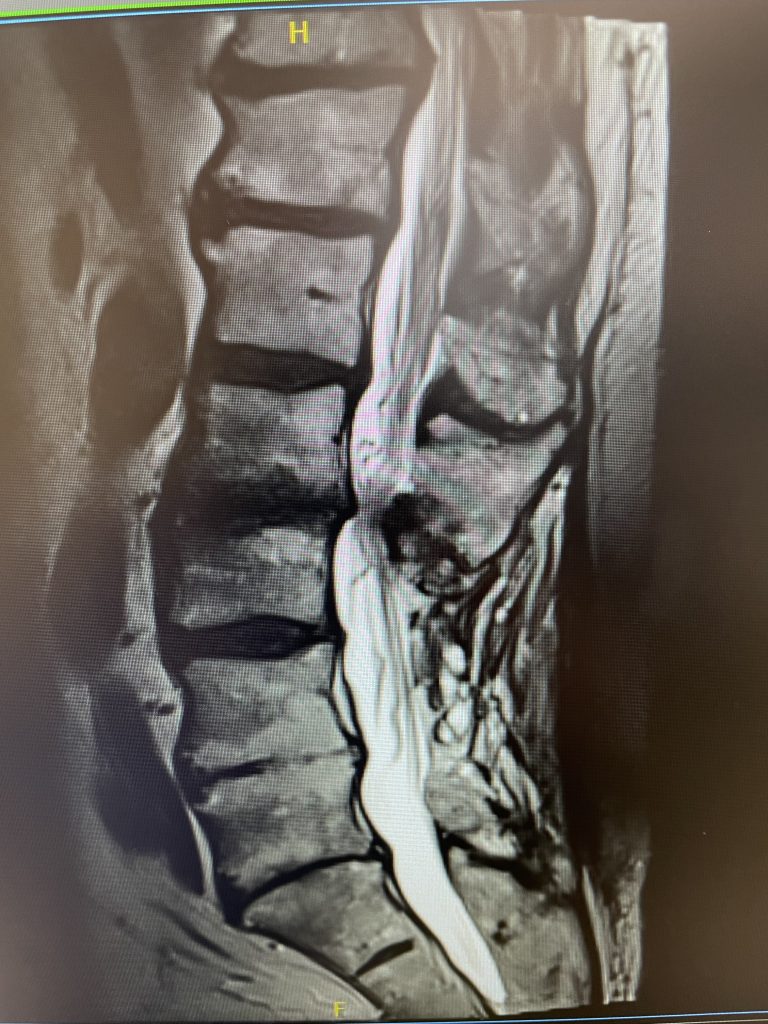

A 69-year-old male presents with chronic low back pain that seems to improve with sitting. The patient had had a prior laminectomy for severe stenosis and in situ fusion five years prior which means that we used bone graft to perform the fusion but no instrumentation. He had done well. Over the last year or so he developed low back pain but no leg pain. The patient had tried all means of conservative management including physical therapy, chiropractic care, acupuncture and epidural injections. Neurologically he was intact. MRI revealed significant stenosis at L2-3 above his prior laminectomy and fusion (Fig 1). We discussed options including surgery. One of the problems we face is a patient with severe stenosis that has severe low back pain with no leg pain. This is particularly challenging when the back pain goes away in flexion or sitting. The quandary is that anecdotally patients with these specific symptoms do tend to improve their back pain after laminectomy, although there are no good studies to support this. Patients with classic neurogenic claudication with pain down their legs when they walk and improved when they sit have a better chance of success. Subjecting a patient to laminectomy for just back pain in the face of having prior surgery puts the patient at risk for not only a potential dural leak because of scarring, but also there may be less of a chance of relieving the back pain than if the patient has leg symptoms. After a discussion, since the patient for the most part is able to manage with conservative treatment modalities is just wait and see over the next three months.